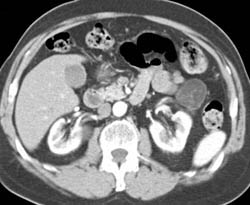

Portal Vein (PV) Thrombosis and Chronic Pancreatitis